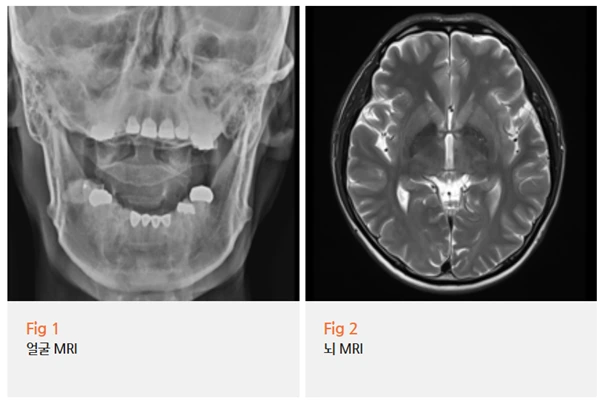

이 환자분은 내원 당시 증상 양상이 삼차신경통과 일치했기 때문에,

당일 뇌 MRI 검사를 먼저 진행했어요.

뇌 병변 여부를 먼저 배제하는 게 중요하거든요.

삼차신경통처럼 보이더라도 뇌종양이나

혈관 기형, 다발성 경화증 같은 원인이 숨어 있는 경우가 있기 때문에,

이를 먼저 확인하지 않고 치료를 시작하면 정말 중요한 걸 놓칠 수 있어요.

다행히 이 환자분의 경우 MRI에서 기질적인 이상은 확인되지 않았어요.

뇌에 특별한 문제가 없다는 결과를 전달드렸을 때,

환자분이 눈에 띄게 안도하시던 표정이 기억나요.

그것만으로도 오셨던 보람이 있으셨던 것 같았어요.